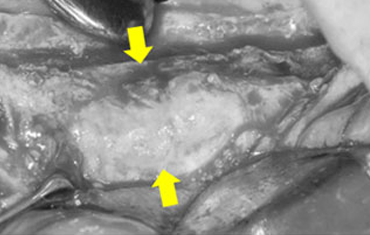

뼈의 소실량이 많은 경우

윗턱뼈 공기주머니에 뼈이식